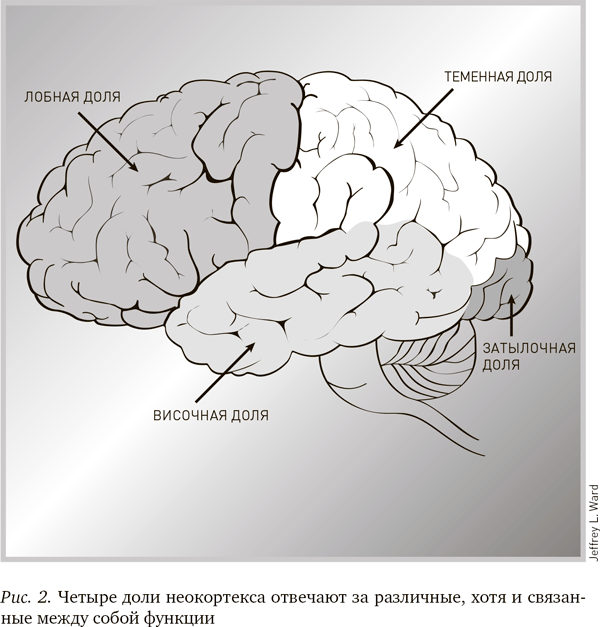

На рис. 2 представлен неокортекс, или новая кора, – внешний слой головного мозга, разделенный на четыре доли. Вообще, неокортекс у человека очень развит. Задача всех долей мозга, кроме одной, – принимать и обрабатывать сигналы от органов чувств; исключение составляет лобная доля, расположенная за лобной костью. Префронтальная кора – самая передняя часть лобной доли – является тем местом, где возникают рациональные мысли. Информация, которую вы в настоящий момент получаете из книги, обрабатывается в префронтальной коре. Повреждение этой области может отрицательно повлиять на вашу способность к планированию и обдумыванию будущего, как это произошло с Финеасом Гейджем. Именно в этой области мозга оценивается получаемая информация и планируются действия.

Теменная доля располагается в верхней части мозга. Правое полушарие контролирует чувственное внимание и образ тела; левая – тонкие движения и некоторые аспекты речи. Повреждение этой области может вызвать множество проблем, в том числе и трудности с распознаванием некоторых частей собственного тела. Затылочная доля располагается в самой задней части мозга и обрабатывает полученную от глаз визуальную информацию. Повреждение этой области может вызвать слепоту и зрительные нарушения.

Височная доля отвечает за речь (только слева), а также за визуальное распознавание лиц и некоторые эмоции. Повреждение этой области может лишить человека речи или способности узнавать знакомые лица.